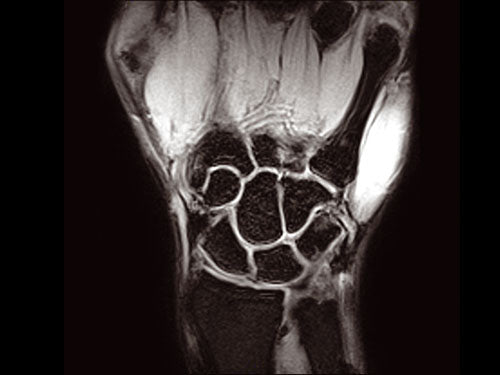

ESAOTE O-SCAN eXP 2016 - Dedicate MRI for Extremities with Cage

ESAOTE O-SCAN eXP  2016 - Dedicate MRI for Extremities

• All Coils (See pictures)